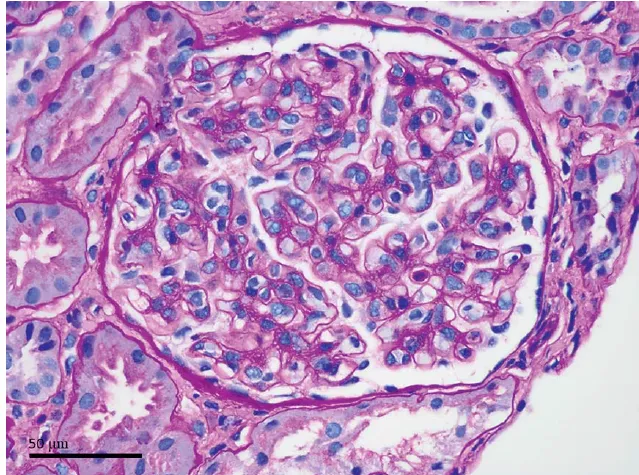

A glomerulonefrite por C3 (GNC3) resulta de ativação descontrolada da via alternativa do complemento e pode simular uma GN pós-infecciosa. O diagnóstico correto depende do reconhecimento do padrão de deposição de C3 e da investigação genética. Com terapias-alvo como o eculizumabe e o iptacopan, identificar precocemente a GNC3 pode mudar o desfecho do paciente.